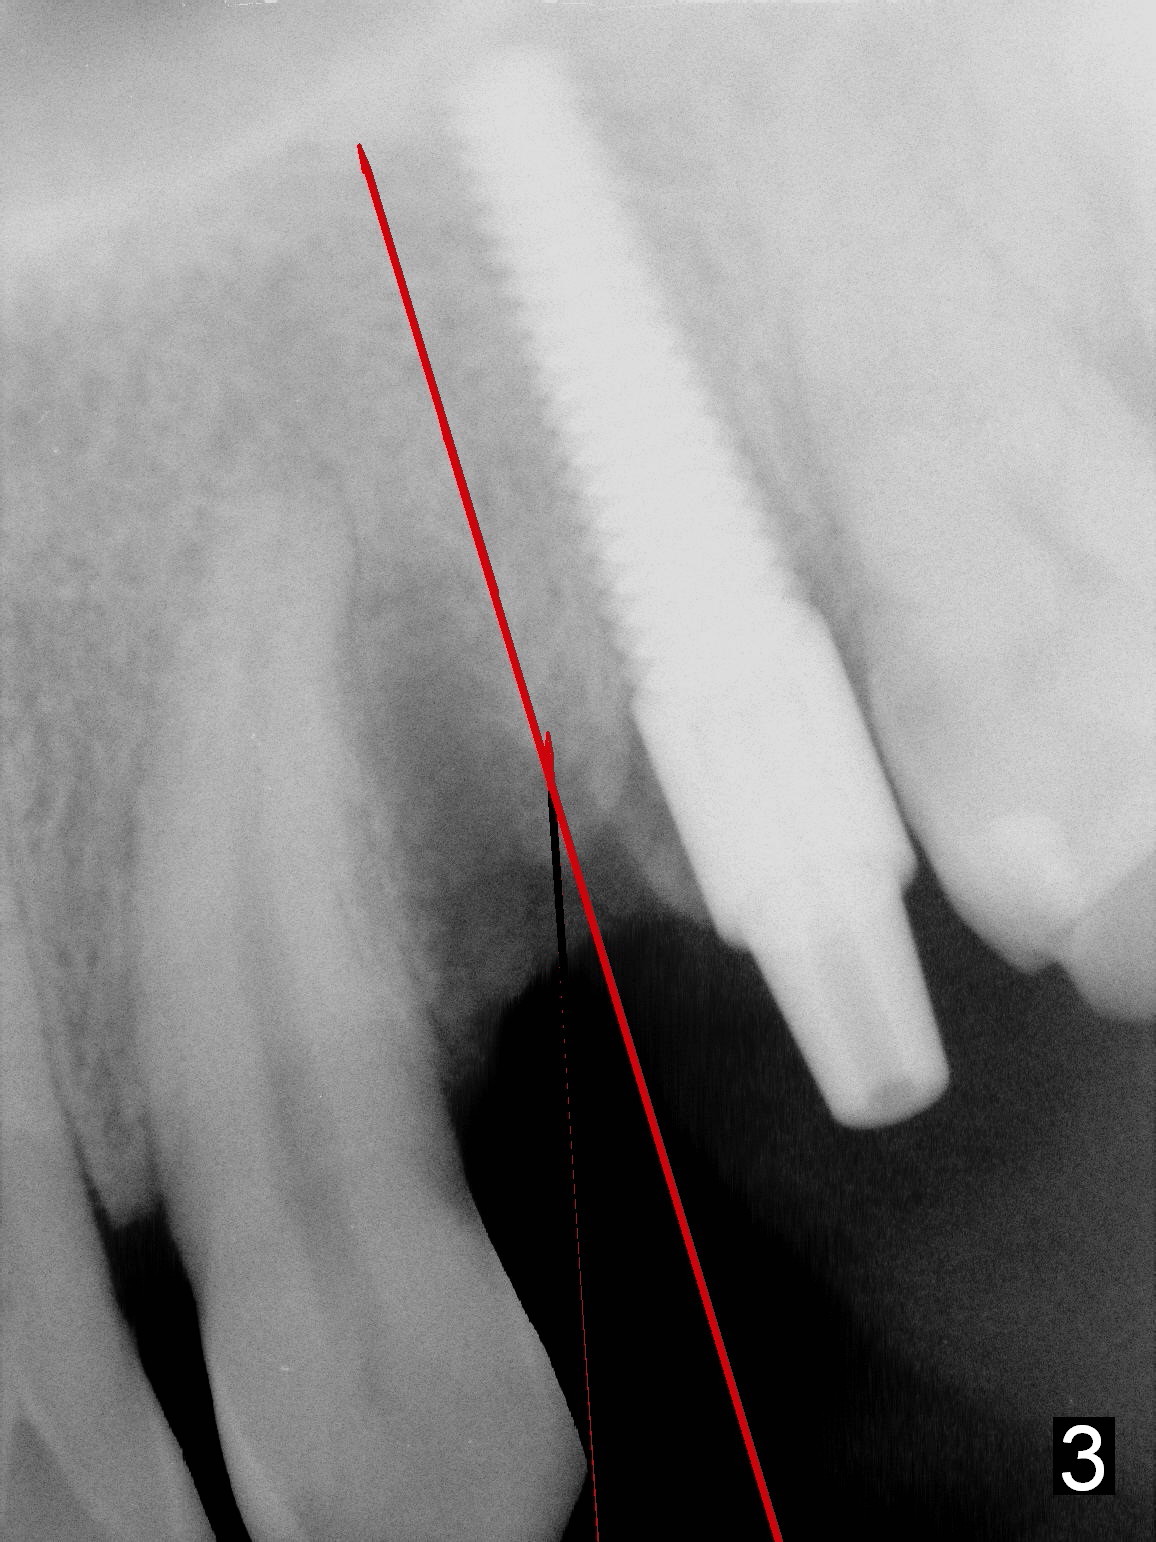

Two and a half months after removal of malpositioned implant at the site of #12 (photos to be taken to show healed socket), a 1.5 mm sharp pilot drill (Tatum, long) will be used (Fig.1 red line) to penetrate the distal slope of the previous osteotomy (photo to be taken). Once the lamina dura is penetrated, the trajectory of the drill is straightened up and deepened until 14 mm from the gingival margin (Fig.2). A 1st intraop PA is taken to confirm the position of the new osteotomy relative to the neighboring structures. If it is correct, deepen the osteotomy until 20 mm (Fig.3) so that it is less likely to be deviated mesially when the diameter of osteotomy is increasing and when an implant (probably 4x20 mm) is being placed. Lean the bur, reamer and implant distally while going deep.